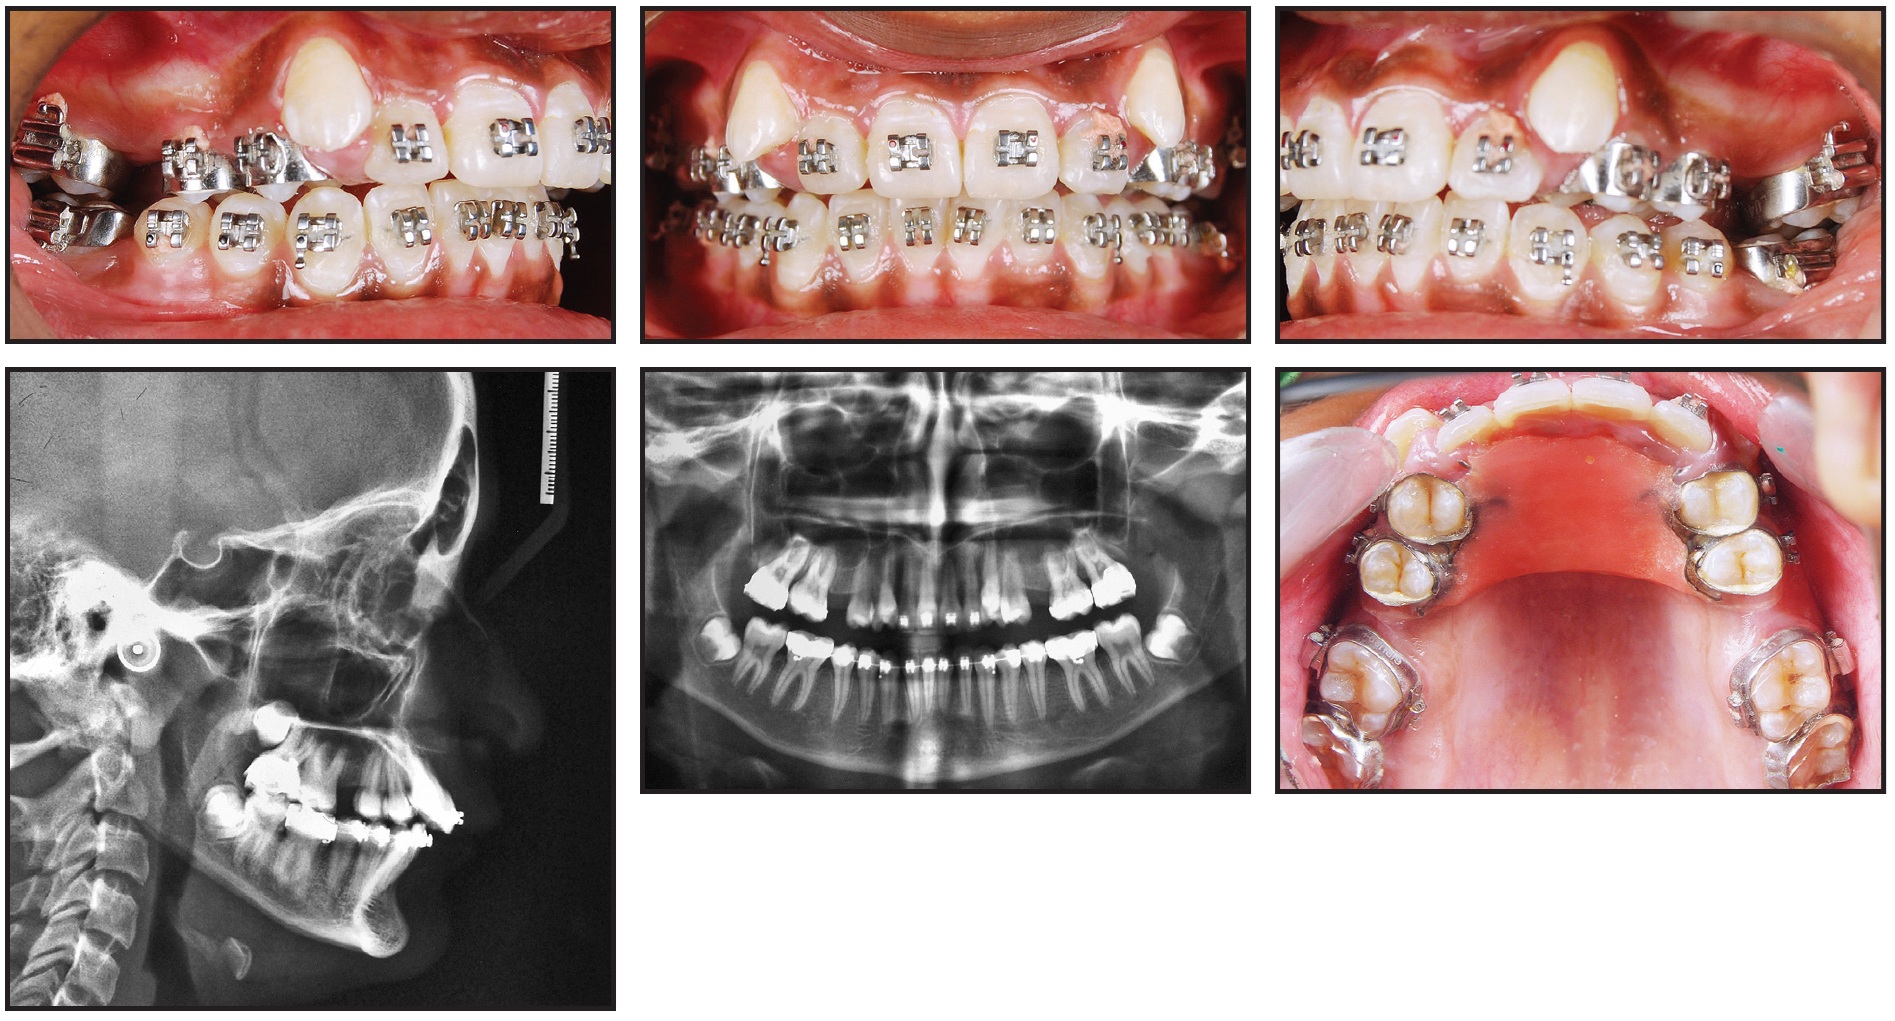

A 17-year-old female presented with high, buccally placed upper canines; retained upper deciduous canines and a retained lower left second deciduous molar; a congenitally missing lower left second premolar; a straight soft-tissue profile; and 11mm of crowding in the upper arch and 7mm in the lower (Fig. 2).

Fig. 2 Case 1. 17-year-old female patient with Class II molar relationship, horizontal growth pattern, retained upper deciduous canines and lower left second deciduous molar, and congenitally missing lower left second premolar before treatment.

Cephalometric analysis indicated a Class II molar relationship over a skeletal Class I base, created by the combination of an orthognathic maxilla and a horizontal mandibular growth pattern (Table 1).

Before active distalization was started, the upper third molars were removed. To begin the first phase of treatment, the Molar Thruster appliance was placed with an active distalizing force; an anterior biteplane was incorporated to disclude the posterior teeth for faster movement (Fig. 3). The lower arch was bonded simultaneously to save overall treatment time, and an .014" nickel titanium archwire was inserted three months later. The pull of transseptal fibers had already caused some distalization of the upper second premolars. After six months of active upper-molar distalization, a bilateral super-Class I molar relationship had been achieved (Fig. 4).

Fig. 3 Case 1. Distalization appliance and anterior biteplane in place.

Fig. 4 Case 1. After six months of distalization.